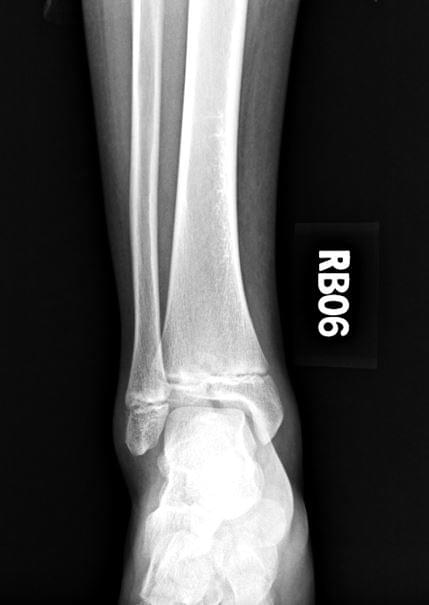

Triplane injury

- 如果關節面位移超過2mm,就需要開刀治療。

- 因為是external rotation造成的,復位時以internal rotation為主。

- 如果關節面沒有辦法closed reduction,要open reduction

- 要跟家屬告知有20%的機會會造成生長板受傷,進而影響到腳踝tilting